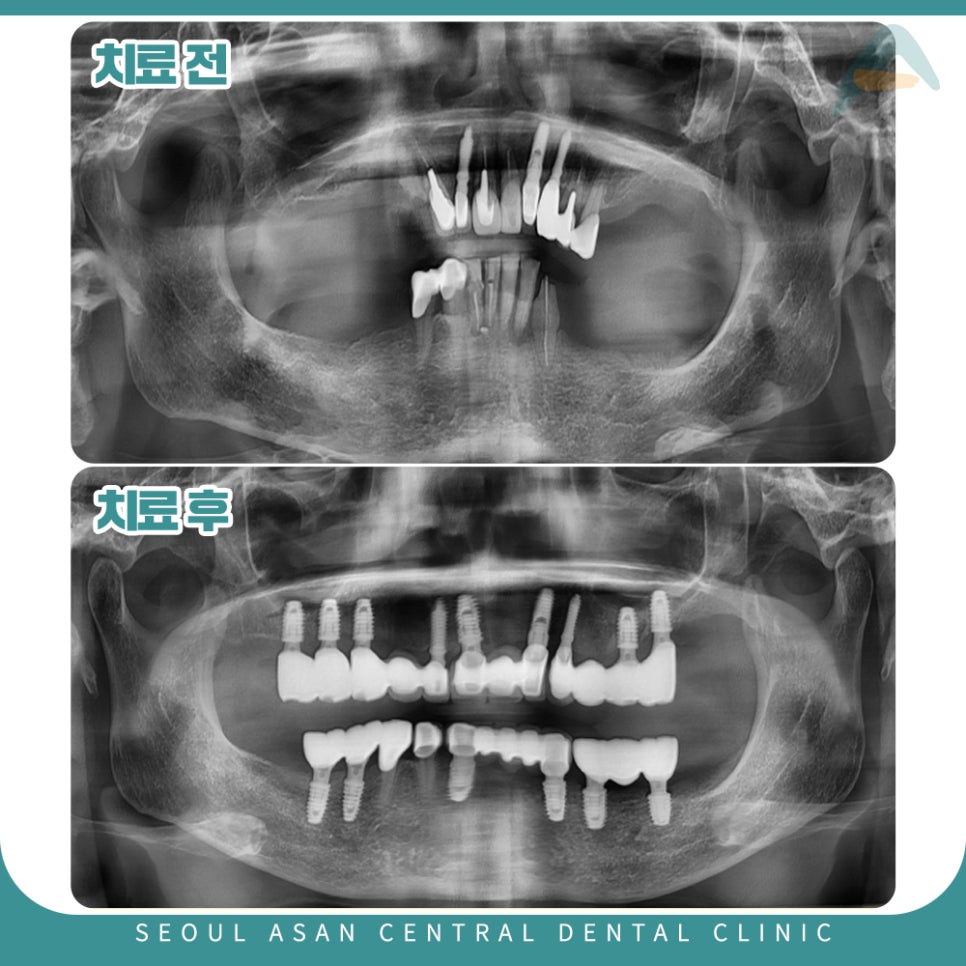

어금니쪽의 치아가 거의 상실된 상태였고,

남아있는 치아들도 전반적으로 치주 상태가 좋지 않아

흔들리는 치아도 다수이며,

염증소견이 있는 치아도 관찰되었는데요.

이런 경우, 상담을 통해 살릴 수 있는 치아를 제외하고는

나머지 치아는 발치 후 임플란트가 필요할 수 있습니다.